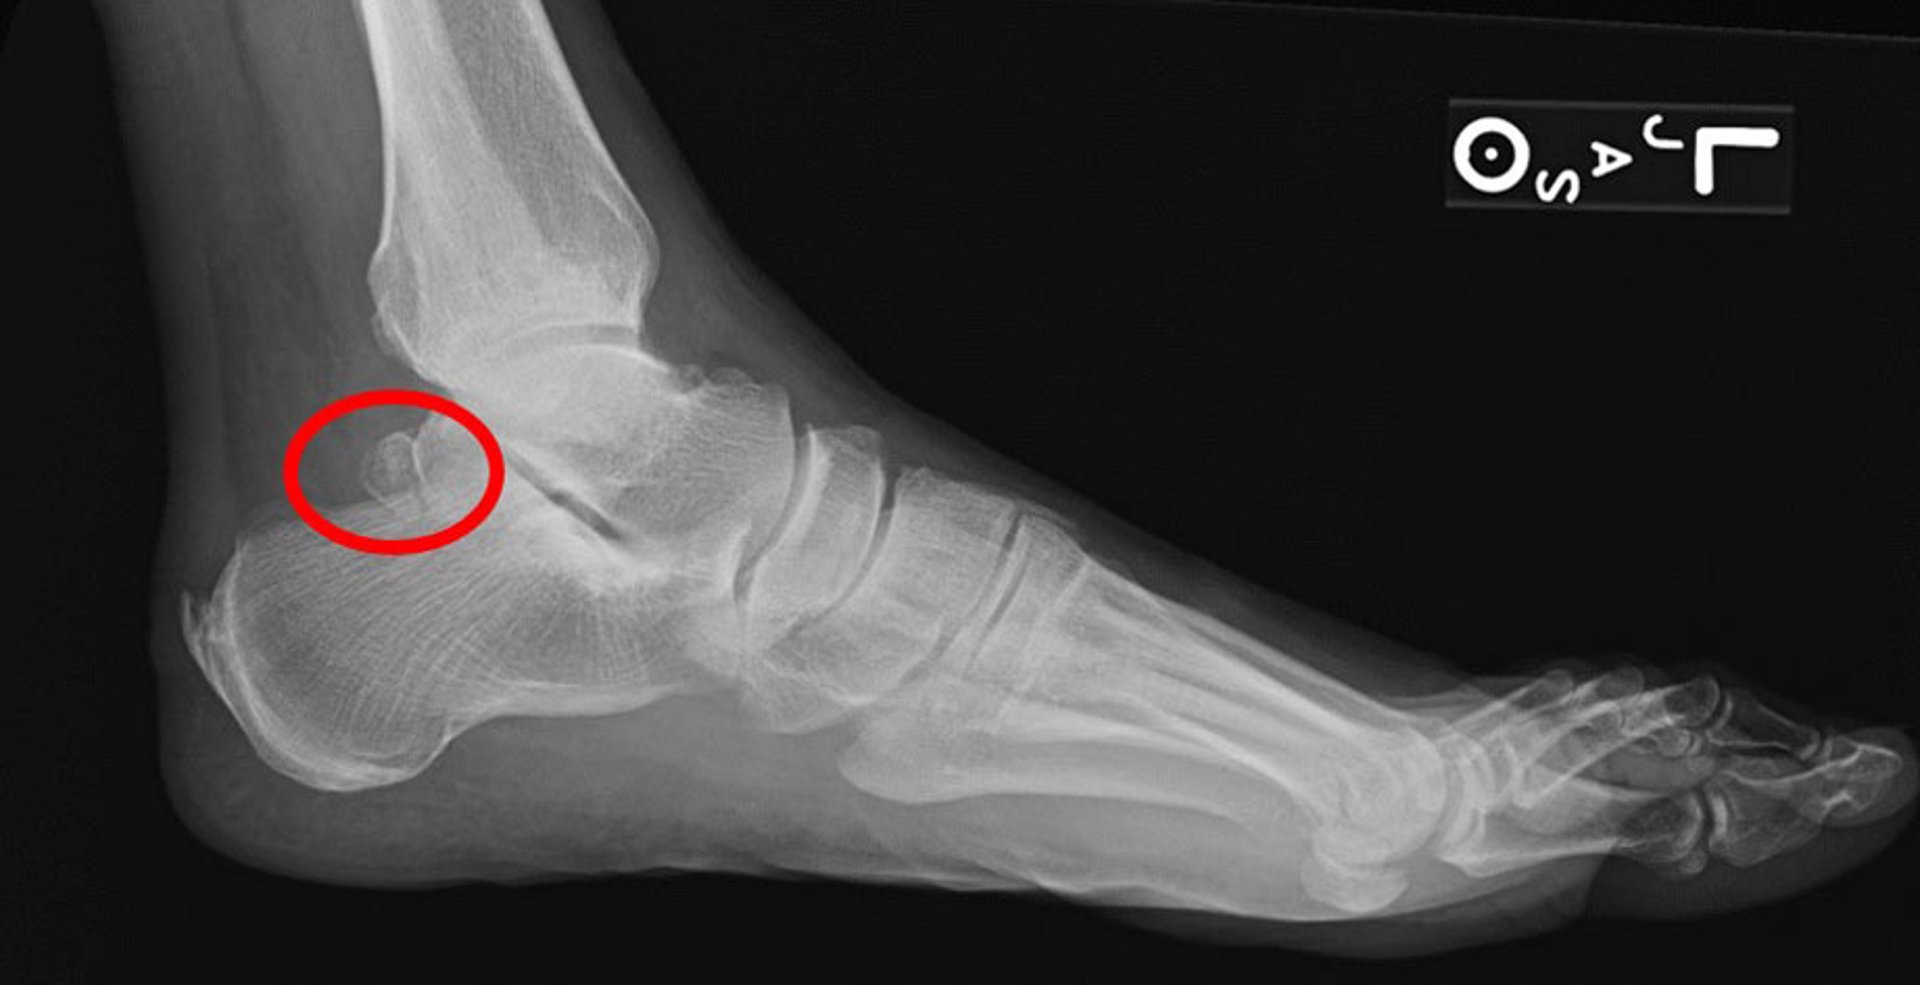

三角骨

此侧位X线片显示距骨三角骨(圆圈所示)。

Image courtesy of James C.Connors, DPM.